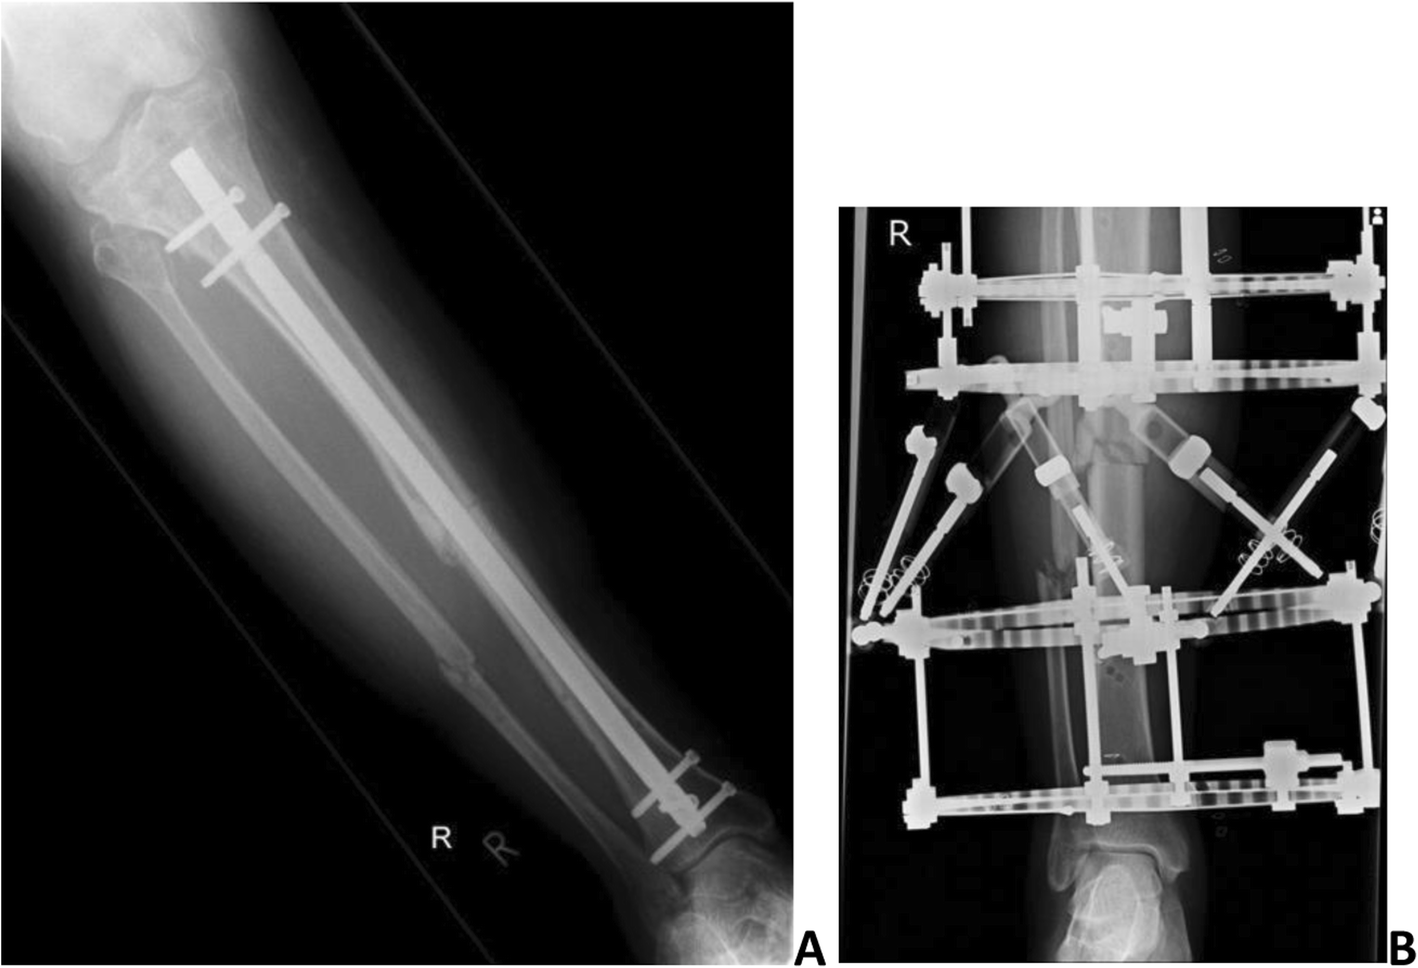

Fig. 1From: Reamed intramedullary nailing versus circular frame external fixation for segmental tibial fractures (STIFF-F): a mixed methods feasibility studya Radiograph showing segmental tibial fracture fixation with IMN. b Radiograph showing CFEF fixationBack to article page